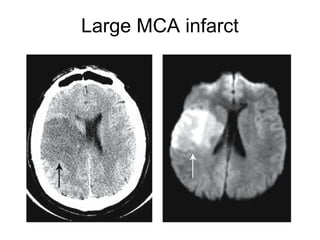

Large MCA infarct

Hyperdense MCA sign